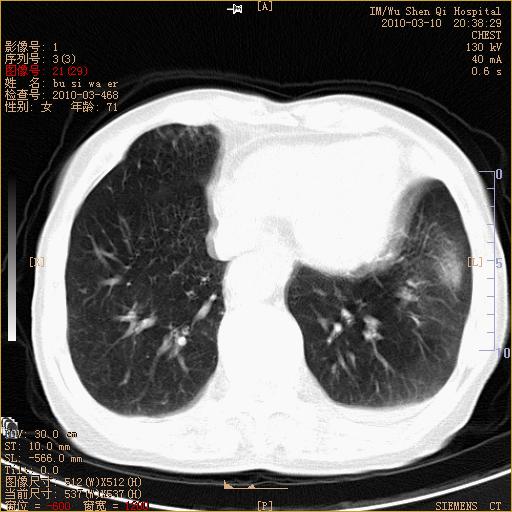

以下是引用随光逐影在2010-3-11 0:41:00的发言:[br]1)考虑左肺及右肺上叶继发性肺结核并左肺炎症感染。2)左侧支气管内膜结核可能;建议必要时行纤支镜检查。3)肺气肿。4)心包膜增厚(或少量心包积液)。5)左侧胸腔积液。